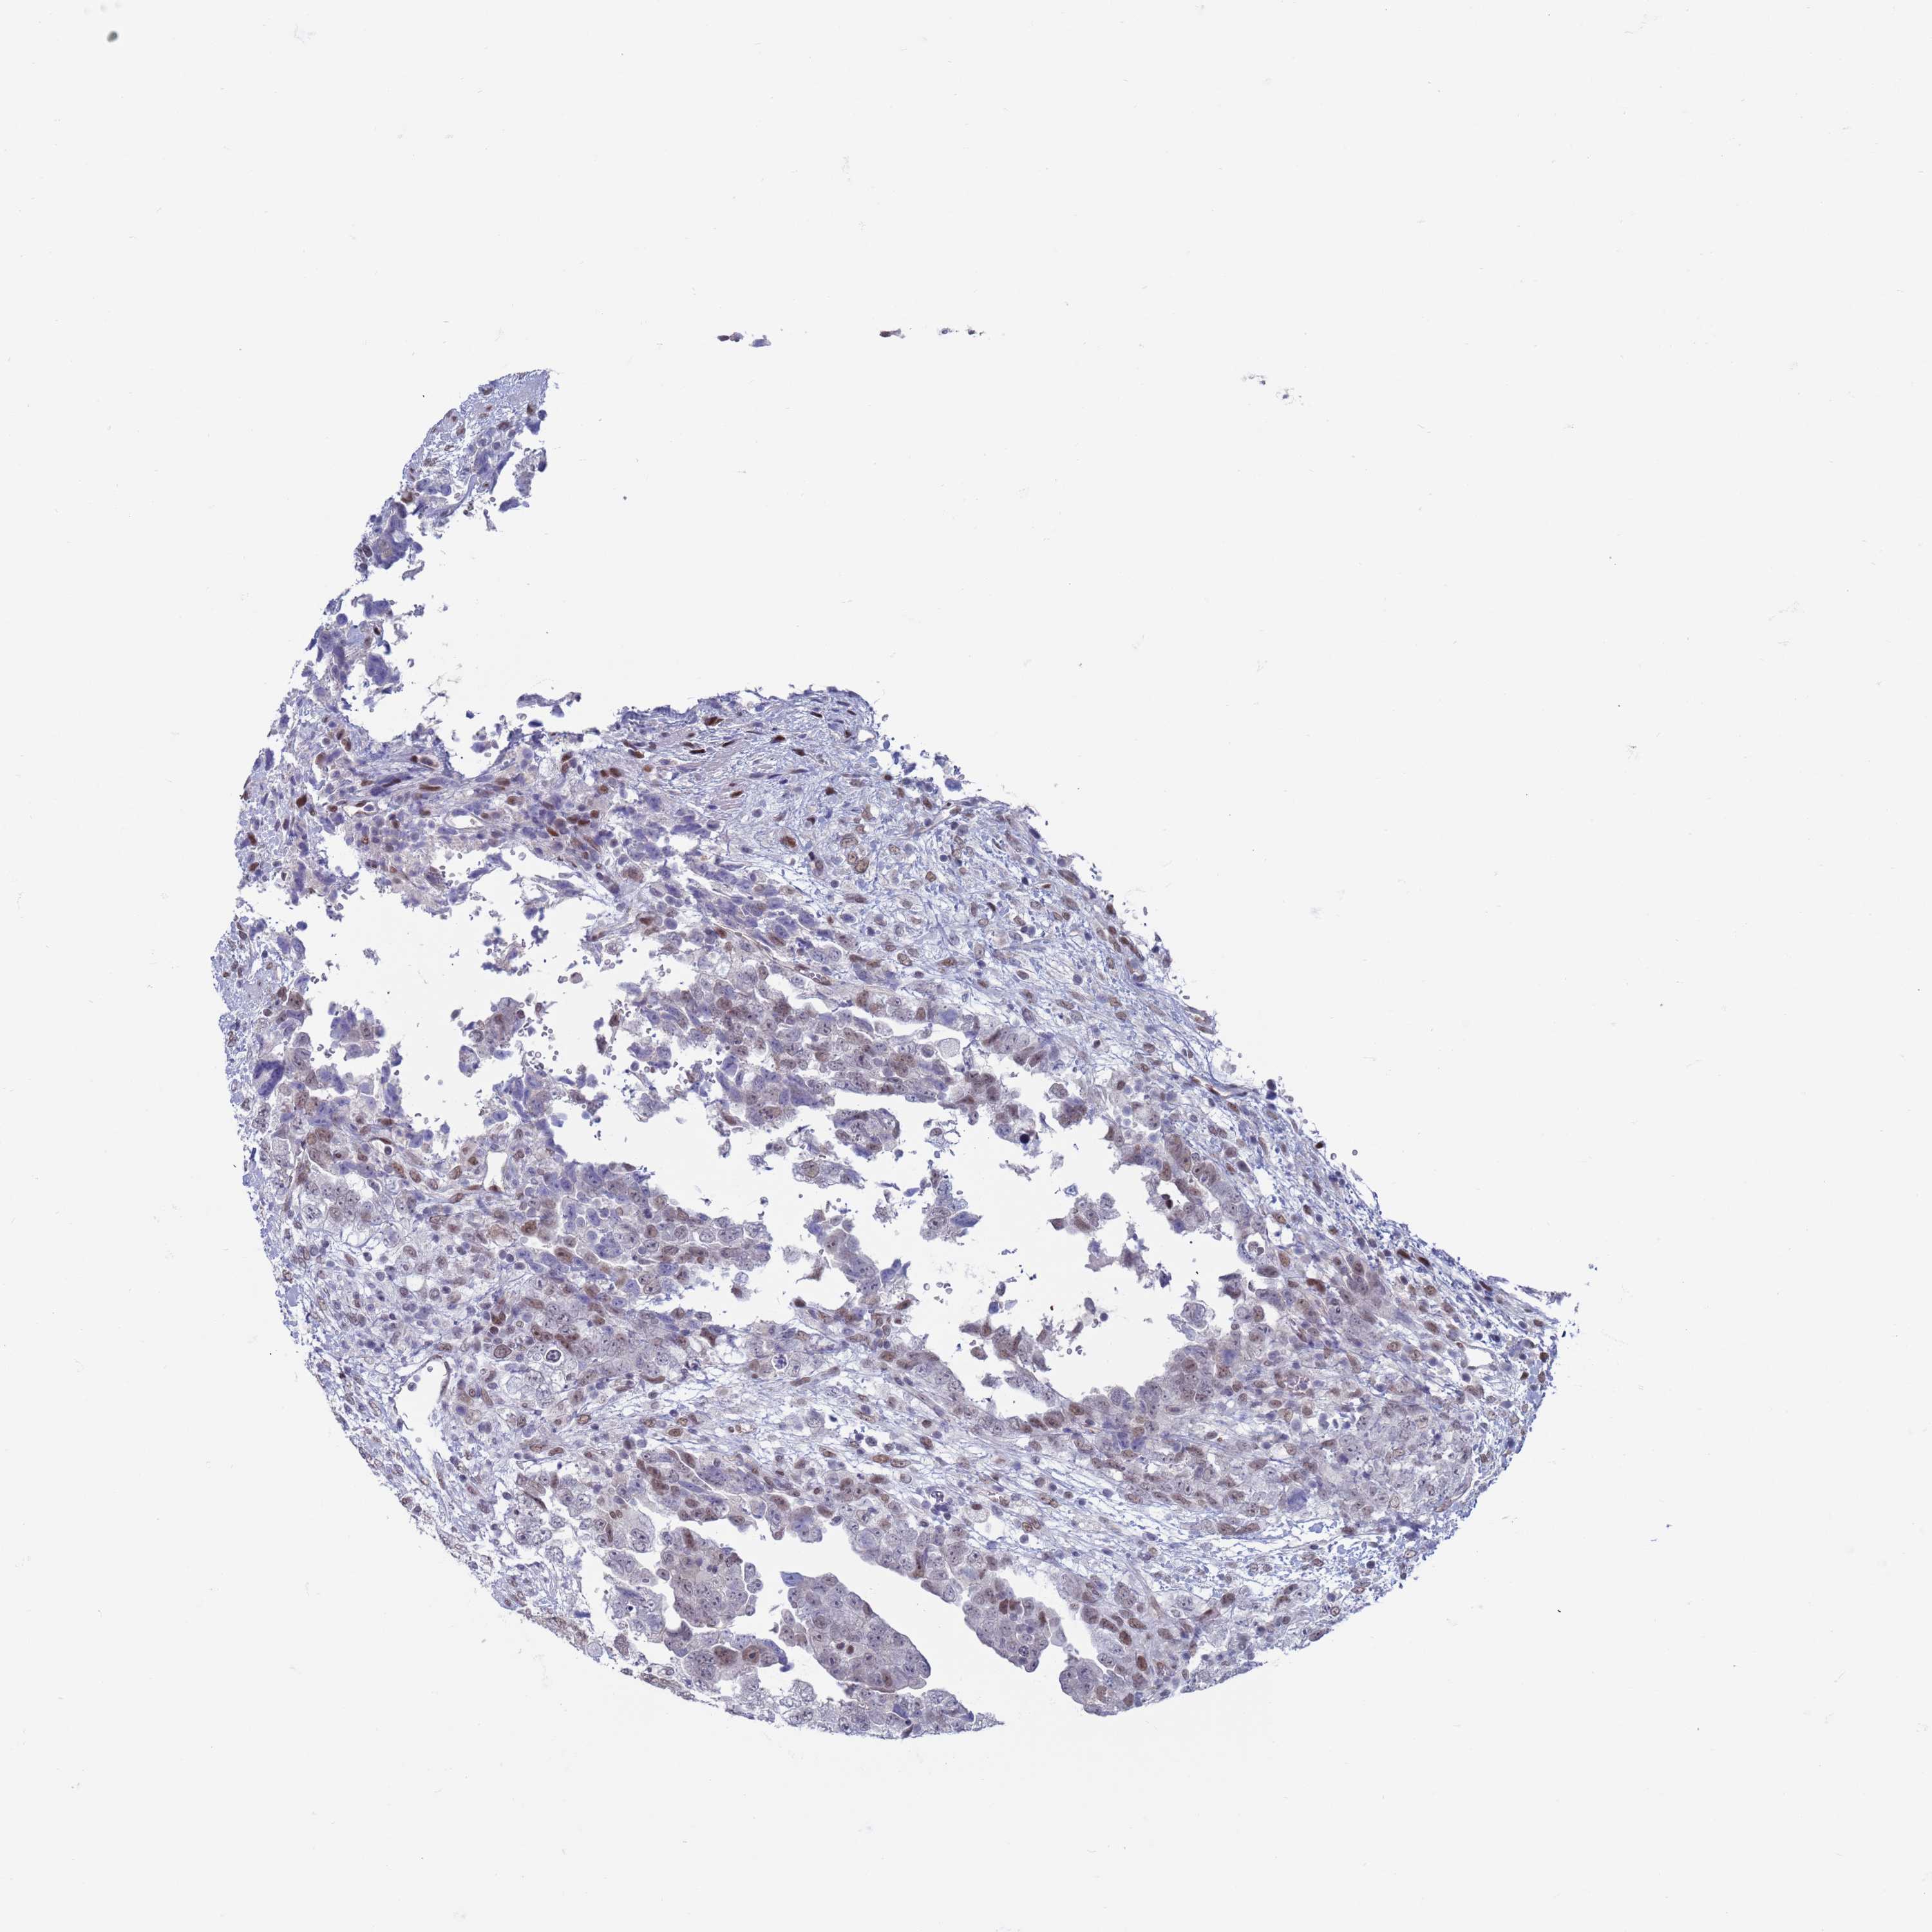

TESTIS CANCER - Protein expressioni

A mouse-over function shows sample information and annotation data. Click on an image to view it in a full screen mode. Samples can be filtered based on level of antibody staining by selecting one or several of the following categories: high, medium, low and not detected. The assay and annotation is described here.

Note that samples used for immunohistochemistry by the Human Protein Atlas do not correspond to samples in the TCGA dataset.

Antibody stainingi

Antibody staining in the annotated cell types in the current human tissue is reported as not detected, low, medium, or high, based on conventional immunohistochemistry profiling in selected tissues. This score is based on the combination of the staining intensity and fraction of stained cells.

Each image is clickable and will lead to virtual microscopy that enables deeper exploration of all samples and also displays staining intensity scores, fraction scores and subcellular localization as well as patient and tissue information for each sample.

Antibody HPA041906

Antibody HPA043552